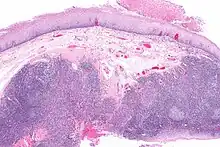

Diagnosis of oral cancer is completed for (1) initial diagnosis, (2) staging, and (3) treatment planning. A complete history, and clinical examination is first completed, then a wedge of tissue is cut from the suspicious lesion for tissue diagnosis. This might be done with scalpel biopsy, punch biopsy, fine or core needle biopsy. In this procedure, the surgeon cuts all, or a piece of the tissue, to have it examined under a microscope by a pathologist.[33] Brush biopsies are not considered accurate for the diagnosis of oral cancer.[34]

With the first biopsy, the pathologist will provide a tissue diagnosis (e.g. squamous cell carcinoma), and classify the cell structure. They may add additional information that can be used in staging, and treatment planning, such as the mitotic rate, the depth of invasion, and the HPV status of the tissue.